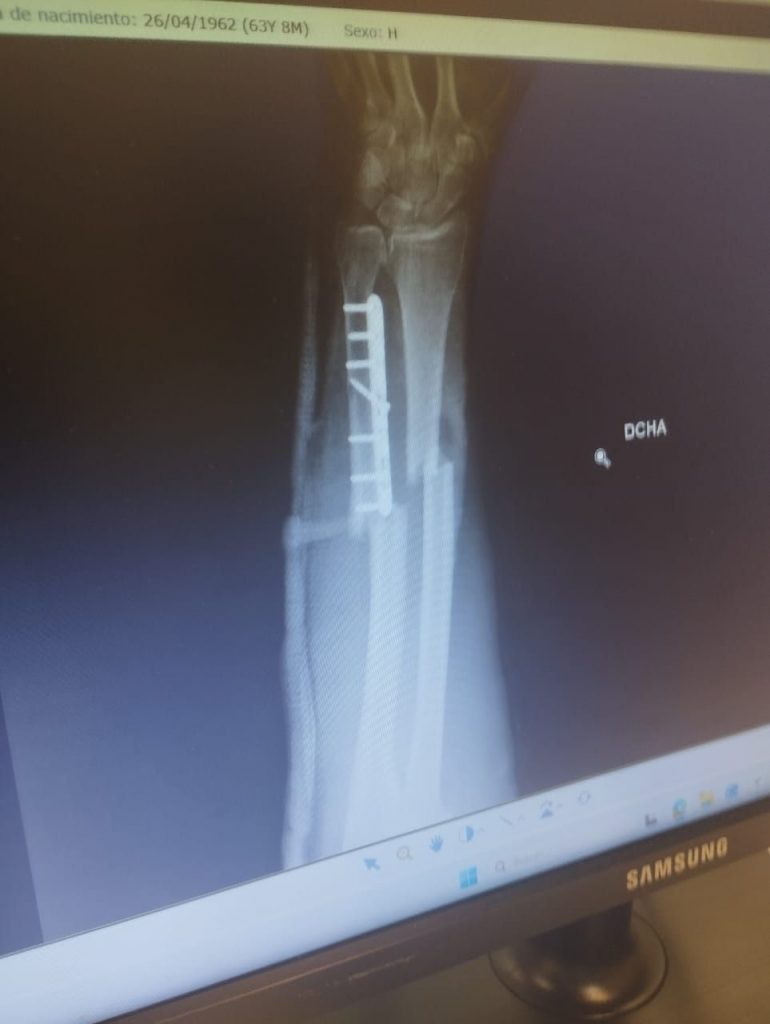

Este señor psicópata tiene orden de alojamiento del local y del propietario del local desde ese día. A día de hoy, 18 de enero, ha quebrantado la orden por tres veces, y ha sido detenido otras tres veces, y puesto en libertad, creando el caos en dicho local y agrediendo al propietario del local con una barra de hierro, partiéndole el brazo por dos lados, ocasionándole dos fracturas muy graves y debiendiendo ser operado con urgencia, una operación que ha conllevado cuatro horas.